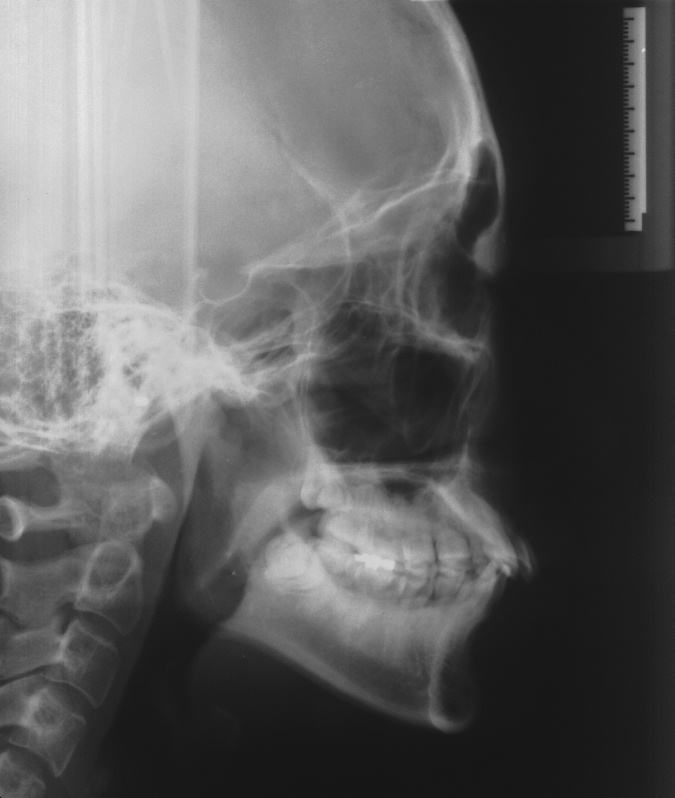

치료 전 사진입니다.